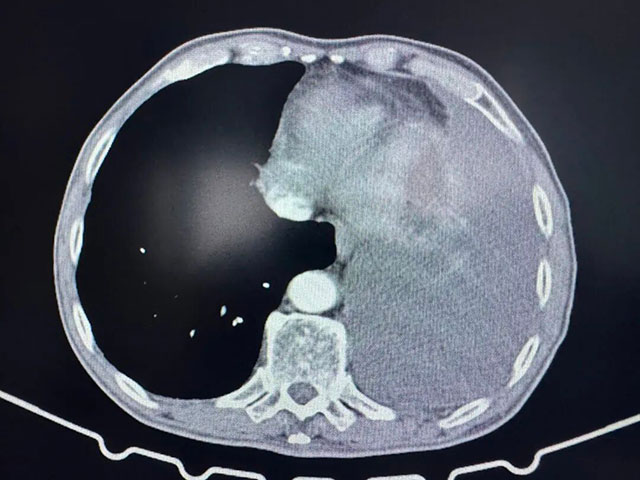

术后胸部CT

7月9日,刘浩副教授手术团队为张爷爷实施胸腔镜下肺部分切除术+胸腔积液清除术+胸膜活检,成功切除了1.5×1.1×1.0cm大小的浸润性腺癌病灶,并清除了胸腔内积液。术后病理提示,肿瘤已侵犯肺膜,属于晚期肺癌,治疗预后不佳。